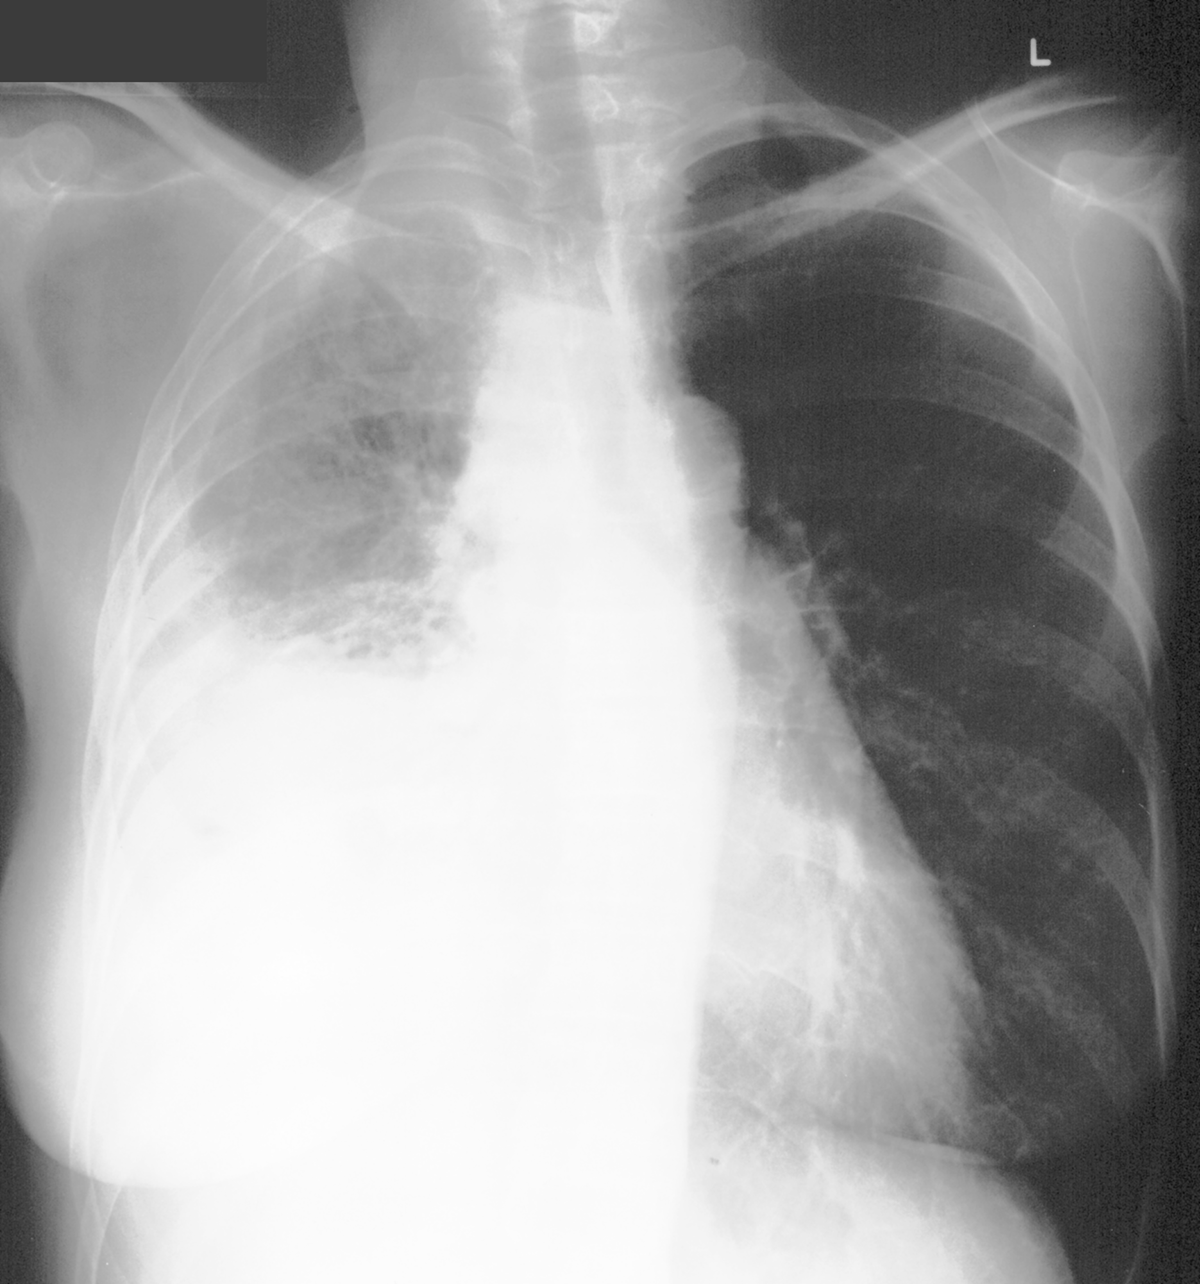

Topic 3

advanced case for effusion

Further Explanation: